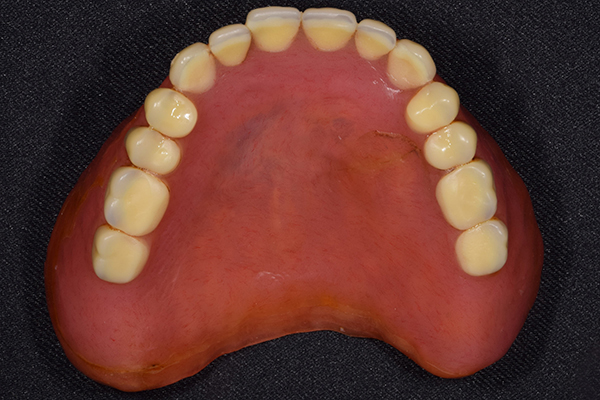

金属を使用して、薄く違和感が少ない入れ歯が完成しました。 また、見た目にも気を使い、バネが見えにくい様な構造にしました。

完成した入れ歯とかぶせ物です。 入れ歯への寛容度が高い患者様でしたので、 金属は使用せず、プラスチックのみで上は仕上げました。 下顎も歯は1本減ってしまいましたが、しっかり 入れ歯が維持できる様な構造にしました。

入れ歯は極力薄くするために金属を使用しました。しっかり噛める様にするため、ノンメタルクラスプデンチャーにはしませんでした。

上の入れ歯(表)

上の入れ歯(裏)